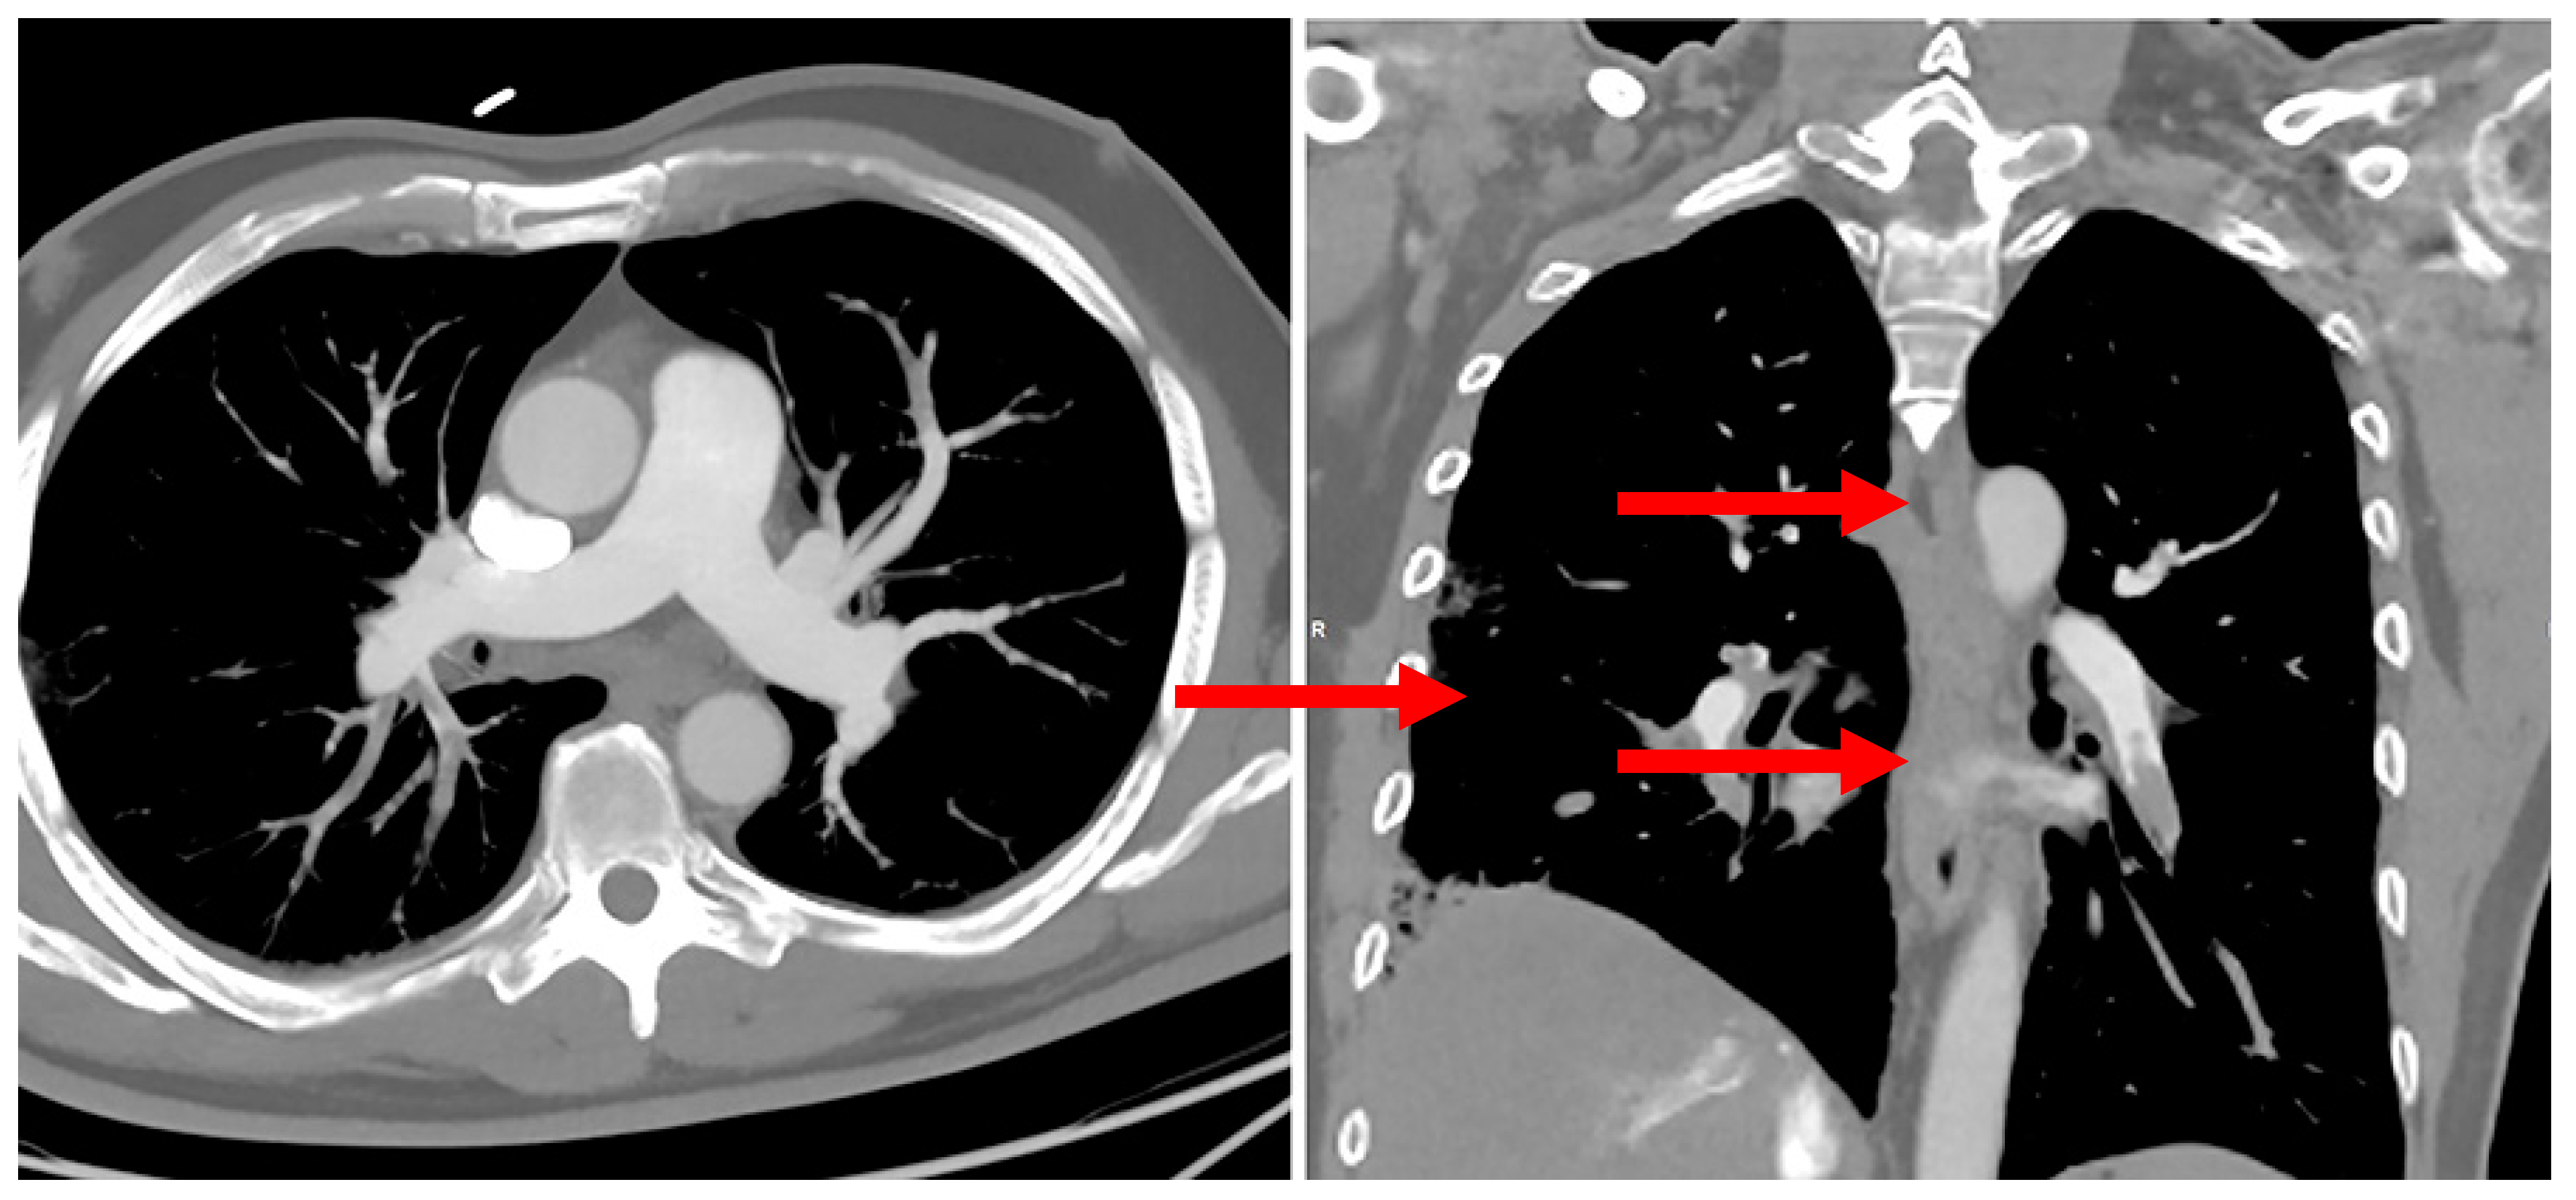

2. Case Report